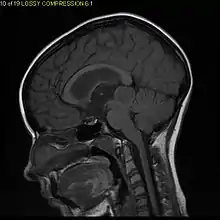

Sagittal T1-weighted MRI showing a well-circumscribed hypointense mass in the tectum (presumably a tectal plate glioma). These lesions are a distinct subset of pilocytic astrocytoma which present with hydrocephalus typically in 6 to 10 year-olds and are rarely progressive lesions. When imaging is characteristic, a biopsy is usually not performed because of the risks to adjacent structures, often shunting to relieve intracranial pressure is the only treatment required.